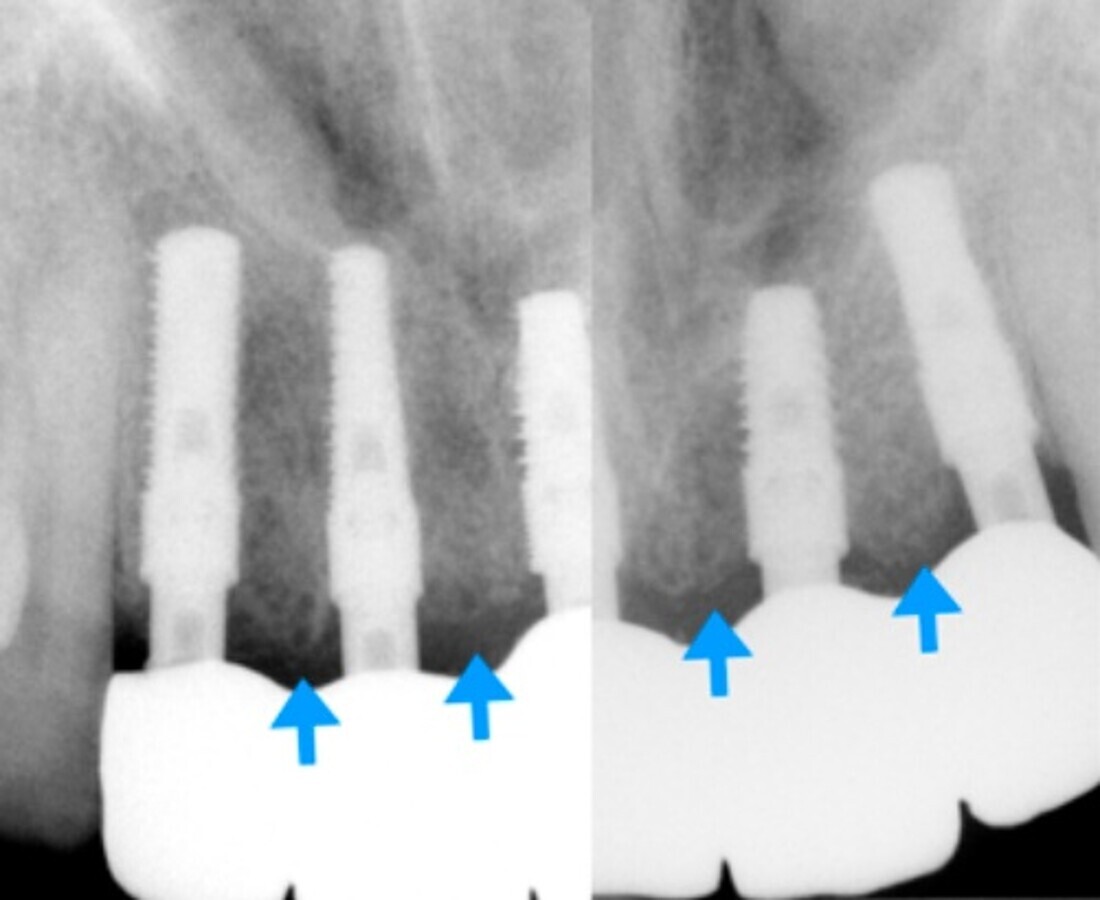

Imagen 6. Radiografías finales del tratamiento con procedimiento de regeneración ósea. Se pueden observar las crestas óseas entre implantes.

En las imágenes se observa el volumen, la regeneración y mantenimiento de las tablas vestibulares de todas las piezas intervenidas, responsables del aspecto de la guirnalda gingival. Sin reabsorción ósea, resultando un tratamiento biológico. “En todo el tratamiento no existe ninguna maniobra clínica, ni del sistema que genere una reacción de defensa que se manifieste como reabsorción, consiguiendo así una integración implanto quirúrgico protético ideal.

La conjunción de conceptos quirúrgicos no invasivos, donde las incisiones son la última alternativa, la no reapertura y el sistema de implantes que no filtra ni sufre micromovimientos, el respeto del espacio biológico que se conforma en el momento de la cirugía, muy similar al que tienen los dientes naturales, nos entrega restauraciones sin reabsorción ósea periimplantar en más de un 90% de los casos.